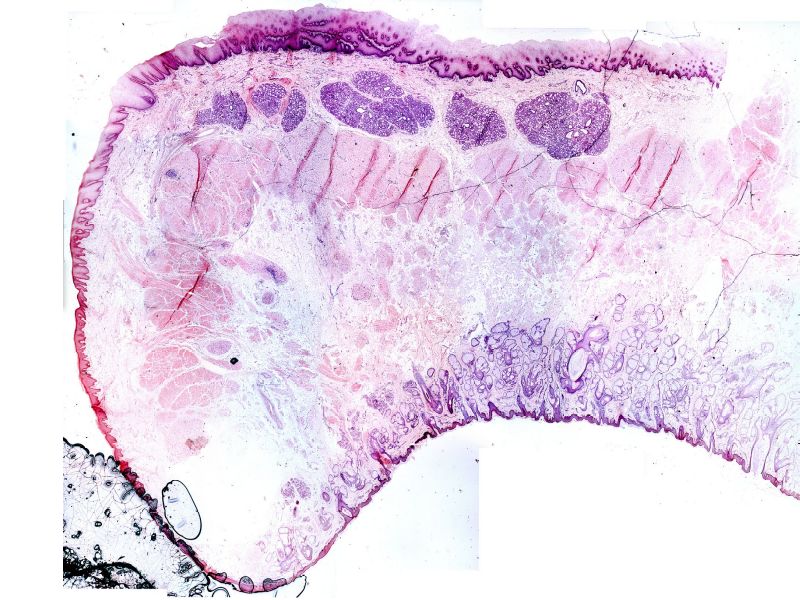

Mammary Gland and Nipple

Mammary gland - slide 57

Nipple - slide 15